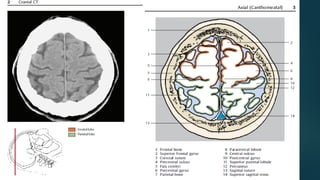

Este documento es el programa para un taller de imágenes del curso de emergencia 2015 impartido por el Dr. Víctor Delgado. El taller se centra en el uso de imágenes médicas para el diagnóstico y tratamiento de pacientes en coma traumático según la base de datos de Marshall. El Dr. Delgado es el único instructor repetido a lo largo del documento.